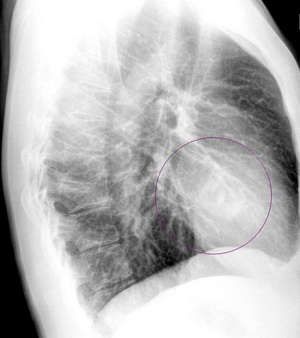

І на підставі даних рентгенограми лікар робить призначення, показане для лікування певної хвороби. У деяких спірних випадках необхідно зробити повторний рентген або іншу його проекцію, наприклад, бічну, як на фото. Це, однак, не повинно приводити Вас у стан паніки. Швидше за все, лікар просто хоче перестрахуватися, а, значить, проявляє увагу до Вашого здоров`я.